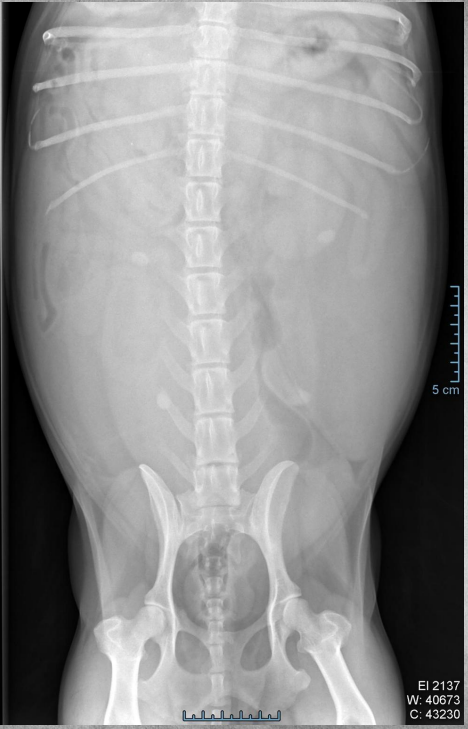

●6 yo castrated male Ragdoll

●Very thin

●Vomiting

● Liver mildly enlarged, rounded with mass effect.

● Kidneys markedly increased in size,

irregularly shaped, displaced ventrally

● Severe bilateral polycystic kidney disease

● Concurrent polycystic liver disease

soft tissue and fluid have the same density so the cysts are all homogenous with the renal tissue. you’d see the cyst pockets on ultrasound.